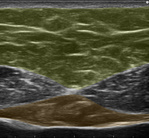

みぞおちに当てて出てくる画像のパターンによって、その人の「これまでの生活習慣」と「今後改善しなければならないこと」が分かります。

【理想的パターン】

【過剰な食べ過ぎと筋トレ不足パターン】

【隠れ肥満(食べ過ぎ)パターン】

【砂糖の過剰摂取と有酸素運動不足パターン】

実際に改善前と改善後を比較すると大きな差が生まれてきます。